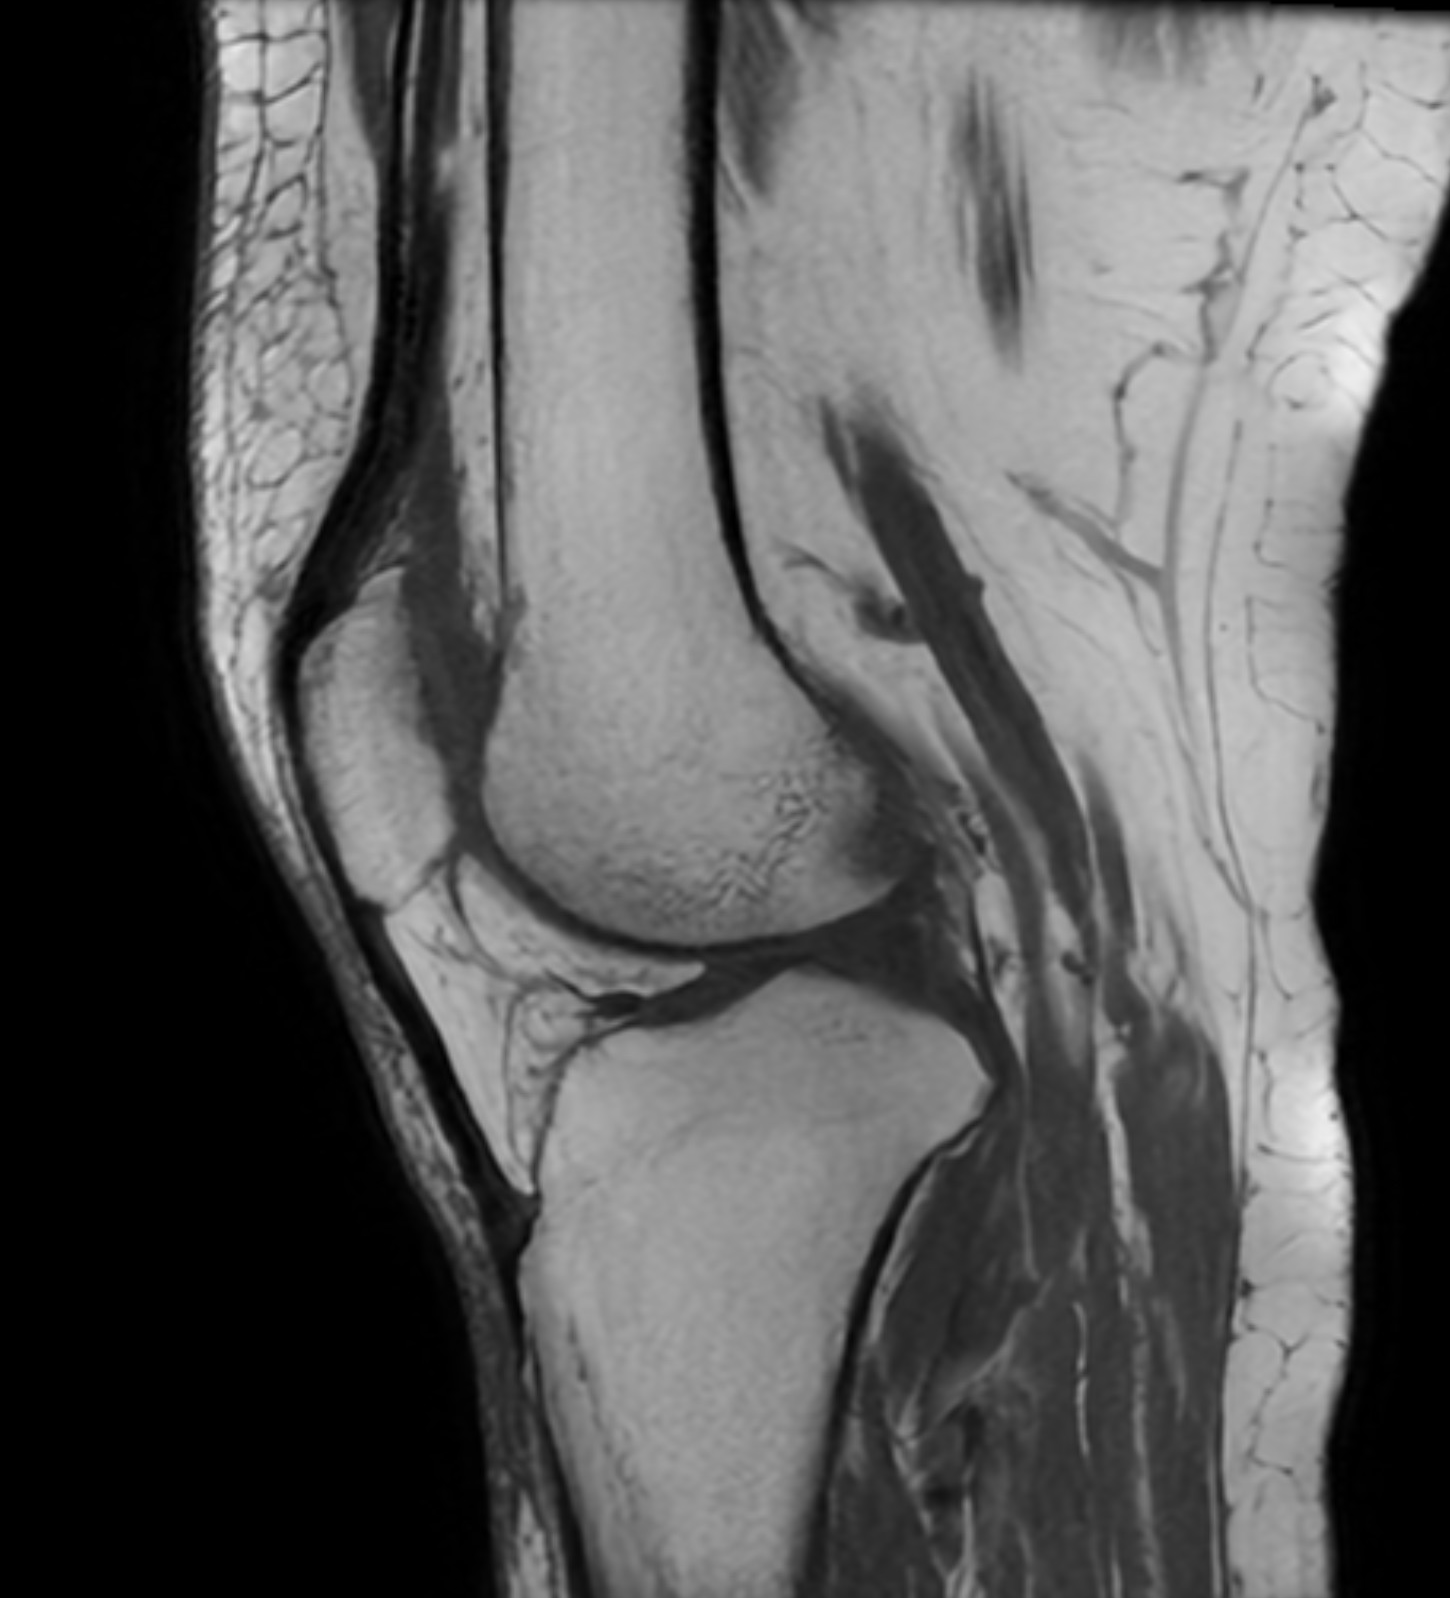

Magnetkameraundersökning (MR) är en avancerad bilddiagnostisk metod som ger detaljerade bilder av knäledens mjukdelar, såsom menisker, korsband, brosk och muskler. Till skillnad från röntgen kan MR visa skador som inte syns på traditionella bilder.

Undersökningen är helt strålningsfri och används ofta när man behöver en mer exakt diagnos.

Exempel på MR-fynd

Vid en MR-undersökning kan man ibland se flera samtidiga förändringar i knät. Ett exempel är degenerativa meniskskador, där vävnaden har förändrats över tid och kan ha sprickor (rupturer).

I vissa fall ses även:

- Bevarat eller lätt påverkat ledbrosk

- Diskreta förändringar i korsband utan total ruptur

- Ökad mängd ledvätska (tecken på irritation)

- Mindre cystor, exempelvis Bakercysta

Dessa fynd behöver alltid tolkas i relation till symtom för att avgöra betydelsen och eventuell behandling.